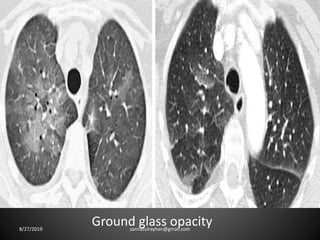

High Attenuation Pattern:

Ground-glass-opacity (GGO):

-Hazy increase in lung opacity without obscuration

of underlying vessels

-'dark bronchus' sign

Ground-glass opacity:

-result of air space disease

i.e.-Filling of the alveolar spaces with pus, edema,

hemorrhage, inflammatory or tumor cells.

or

-result of interstitial lung disease

i.e.-Thickening of the interstitium or alveolar

walls below the spatial resolution of the HRCT as

seen in fibrosis.

Ground glass opacity8/27/2019 zannatulrayhan@gmail.com